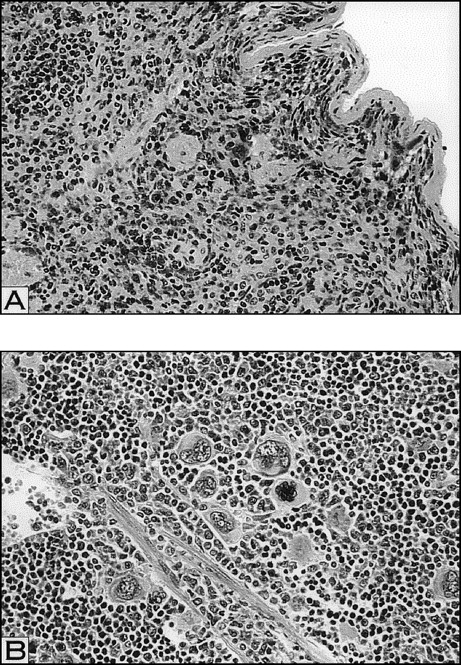

We next examined the number and morphology of megakaryocytes within the spleens and marrows of the various thrombocytopenic mice. Compared with the control spleen samples, the spleens of the irradiated groups were hypocellular. Thorough examination of the entire spleen sections from the irradiated mice demonstrated very few, if any, visible megakaryocytes (Fig 6 and Table 3). In contrast, examination of spleen sections taken from both 5 d RAMPS and W/B F1 males showed a substantial increase in overall cellularity and megakaryocyte numbers compared with controls (Fig 6 and Table 3). This, together with their larger megakaryocyte size and increased spleen weight (Fig 3), indicated that megakaryocyte mass in the entire spleens of these mice was the highest among the thrombocytopenic mice. Examination of the spleens from 1 d RAMPS mice showed a slightly increased number of megakaryocytes per 10 hpf compared with that of controls (Table 3). The number of megakaryocytes per field within the marrow of the control mice was markedly higher than that of the spleen. Megakaryocytes within the marrow of 5 d RAMPS and W/B F1 males were also approximately 90% and 75% greater in number, respectively, and larger in size than controls (data not shown), consistent with earlier studies,25 26 whereas megakaryocyte numbers were only approximately 40% higher in 1 d RAMPS mice than in controls (data not shown). Although megakaryocytes could be observed in some portions of the marrow in the irradiated mice, the overall number was reduced compared with controls (data not shown). In general, changes in the marrow megakaryocyte mass of thrombocytopenic mice seemed to be less pronounced than in the spleens.

Histopathological analysis of megakaryocytes in spleens of irradiated (A) and 5 d RAMPS mice (B). Megakaryocyte numbers appear markedly decreased in irradiated mice, whereas the 5 d RAMPS mice appear to have marked increases in the spleen sections. Increased numbers of megakaryocytes appear associated with increased size (hematoxylin and eosin; original magnification × 100).